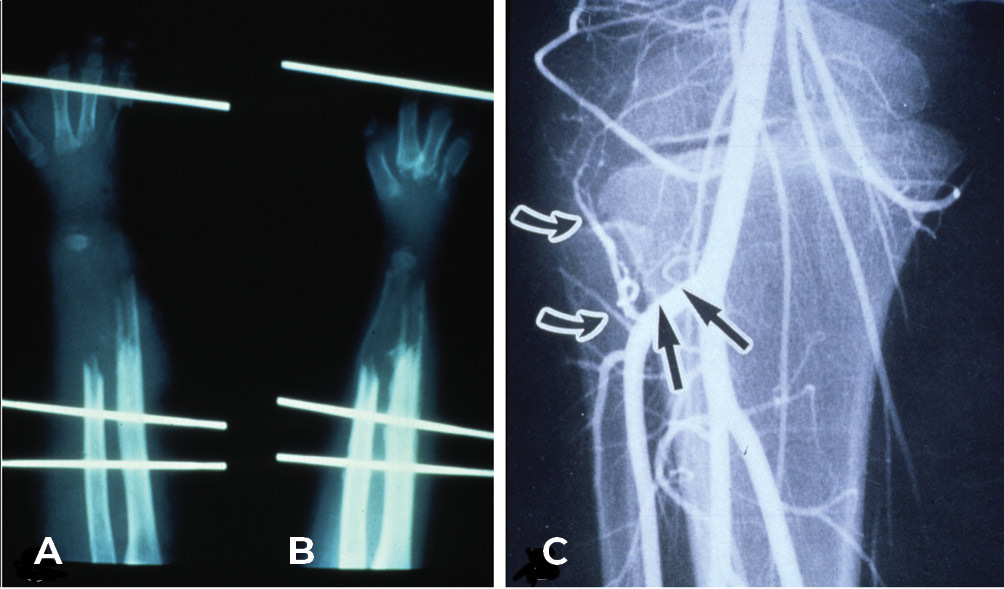

On 20 January 1973 the free groin flap was transferred successfully at PANCH for the first time.2,3 One week later, a 19-year-old young man was admitted to the same hospital with a shotgun injury to his left leg (Figure 1A). The wound included skin, most of the anterior muscle compartment and a 12.5 cm defect of the tibia (Figure 1C).

The foot was sensate and the fibula was intact. So we set about reconstruction. The defect was debrided, healed initially with a split skin graft and then a free groin flap was attempted but abandoned because the groin vessels were very small and the recipient anterior tibial vessels badly damaged. However, because we had performed a lateral to medial dissection of what was now an expanded iliofemoral flap,2 that included the superficial inferior epigastric as well as the superficial circumflex iliac vessels, we were able to tube the flap and transfer it in stages to the leg (Figure 1B).

A two-stage transfer of the ipsilateral fibula was then attempted by our orthopaedic team, based on a muscle pedicle and fixed to the tibia with screws. Unfortunately, the bone failed to knit at the upper end. It developed a pseudarthrosis and the patient was left with a flail leg (Figure 2). Amputation was recommended but ‘if a skin flap can be transferred successfully with microsurgery why not bone, and which one?’

Both legs were placed in above-knee casts and the postoperative course was uncomplicated. The cast was removed from the donor right leg at three weeks and left on the other for six months. At five weeks an angiogram revealed a patent anastomosis (Figure 4A) and a bone biopsy revealed living osteocytes. At nine months the patient received an injury to his transplant when a door of a vehicle was slammed on his leg. The leg was a bit sore but he was able to walk with some discomfort. He presented a month later when an X-ray revealed not only a stress fracture, but showed callus and bony union in this transplanted fibula (Figure 4B)! Thereafter, remarkably in just two months, the fibula doubled its diameter! Subperiosteal thickening had occurred along its entire length, like wax dripping down a candle (Figure 4C). Notably, when reviewed 40 years later the original medullary cavity of the transplanted fibula was still visible (Figure 4D), with normal activity in both legs (Figure 5).6